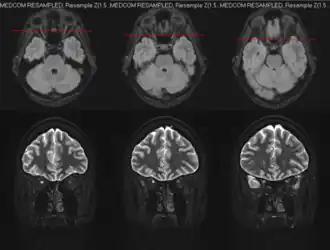

Neuritis optica[2][3] is een ontsteking van de nervus opticus. In gevallen waarin het intraoculaire (in het oog gelegen) gedeelte van de nervus opticus niet betrokken is, spreekt men van neuritis retrobulbaris (retro = achter, bulbus = (oog)bol). Bij dit type is er geen sprake van papiloedeem, bij neuritis optica sensu stricto wél. De aandoening wordt ook wel neuritis axialis genoemd, omdat met name de middelste (axiale) zenuwvezels van de oogzenuw zijn aangedaan. Deze zenuwvezels vormen de verbinding van de gele vlek met de hersenen, waardoor patiënten met een neuritis optica een sterke visusdaling krijgen in het midden van het gezichtsveld, waarbij de gezichtsscherpte erg laag kan zijn. Naast de visusdaling hebben patiënten ook problemen met het kleuren zien.

Het stellen van de diagnose is veelal moeilijk. Een oogarts zal in het beginstadium geen afwijkingen kunnen vinden aan het oog, ook niet bij het oogspiegelonderzoek. Na enige weken kan bij inspectie van de oogfundus een karakteristieke verbleking van de blinde vlek, de uittreedplaats van de nervus opticus uit het oog, worden gezien, en dan met name van de helft die niet aan de neuszijde zit. Dit wijst op atrofiëring van de aldaar aanwezige zenuwvezels.

Een belangrijke oorzaak van neuritis optica is multiple sclerose. Bij 30% van de gevallen waarvan sprake is van MS, is neuritis optica het eerste symptoom van de aandoening. De aandoening treedt dan meestal eenzijdig op en gaat vaak vanzelf over, alhoewel een hoge dosis intraveneuze corticosteroïden het genezingsproces bespoedigt. Een tweede belangrijke oorzaak van neuritis optica is alcoholmisbruik. Als gevolg hiervan treden namelijk diverse vitaminedeficiënties op, waarvan een vitamine B1-deficiëntie verantwoordelijk wordt gehouden voor neuritis optica, welke in dit geval tweezijdig optreedt. Ten slotte kunnen ook veel virale en immunologische ontstekingen leiden tot een neuritis optica.